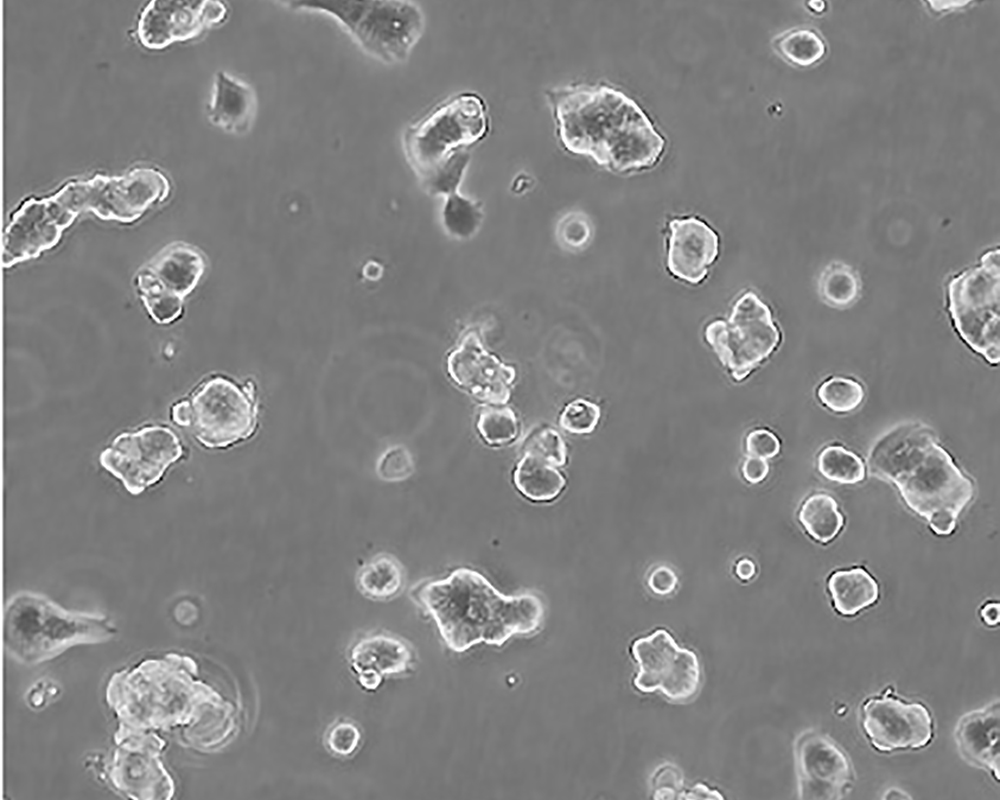

生長特性 adherent

形態特征 epithelial

細胞描述 該細胞產生高水平的黏液素MUC-1 mRNA,低水平的MUC-2 mRNA,但不表達MUC-3基因;表達雌激素受體。

細胞傳代步驟 如果細胞密度達80%-90%,即可進行傳代培養。1. 棄去培養上清,用不含鈣、鎂離子的PBS潤洗細胞1-2次。2. 加2ml消化液(0.25%Trypsin-0.53mM EDTA)于培養瓶中,置于37℃培養箱中消化1-2分鐘,然后在顯微鏡下觀察細胞消化情況,若細胞大部分變圓并脫落,迅速拿回操作臺,輕敲幾下培養瓶后加少量培養基終止消化。3. 按6-8ml/瓶補加培養基,輕輕打勻后吸出,在1000RPM條件下離心4分鐘,棄去上清液,補加1-2mL培養液后吹勻。4. 將細胞懸液按1:2到1:5的比例分到新的含8ml培養基的新皿中或者瓶中